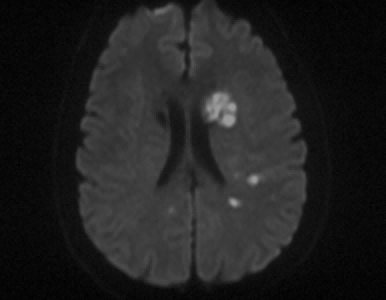

埃斯科核心实验室(IsCore image corelab) 是晓得(北京)商业发展有限公司旗下 的独立第三方核心实验室。由经验丰富的临床专家团队和影像放射专家团队组成, 致力于帮助临床医生和医疗领域的公司进行细致的、标准的、规范的影像管理和 判读。IsCore 影像实验室提供的影像判读数据已经为多家医疗机构的科研课题提 供数据支持,同时也已经协助国内外数个产品研发上市提供科学帮助。我们实验室的影像评价者均在国内顶尖专科医院接受过临床影像专业的系统学 习与规范培训,有多年的临床工作经验,以及强大的技术支持,能准确判读 MRI, HRMRI, DSA, OCT, CFD, VU 等影像,给出标准规范的报告结果,最低限度减少 了人为因素对试验结果的影响有助于科研成果产出和产品研发。